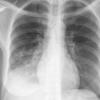

Case 2 Lingular pneum PA

Date: 04/17/2005

Views: 6418